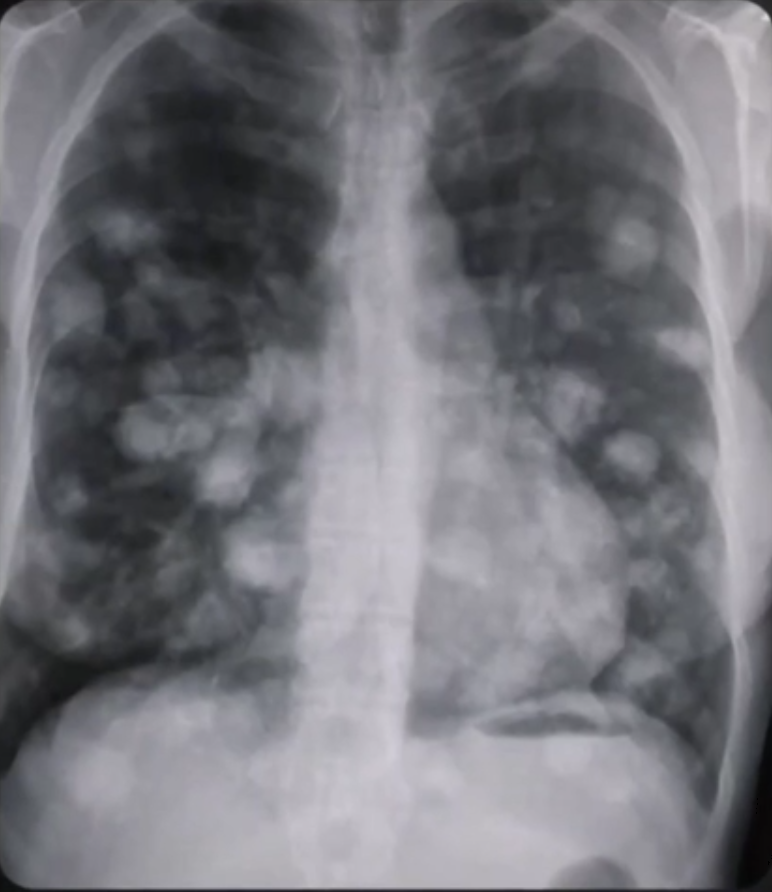

Avant sa rencontre, Higdon souffrait depuis longtemps de douloureux calculs rénaux, ainsi que de problèmes pulmonaires résultant d’une tuberculose contractée des années plus tôt. Or, ces deux affections ont disparu après l’événement. Une radio de ses poumons a montré qu’il n’y avait plus aucune trace des poumons abîmés présents sur des radios antérieures, sachant que les poumons abîmés par la tuberculose ne peuvent pas se reconstituer seuls quand l’affection est terminée, ils restent endommagés à vie. Il s’agit là d’un type de preuve difficile à remettre en question ou à falsifier.